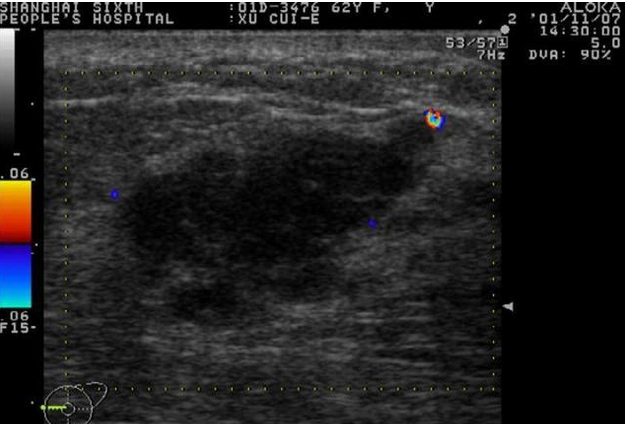

首先需要看结节的大小和形状,如果结节比较小,形状规则,边界清晰,一般是良性的,可以3-6个月随访观察;如果边界毛糙,欠清晰,形态不规则,呈“螃蟹足”的改变,那么恶性的可能性比较大。

规则、椭圆形的良性肿瘤

不规则的“蟹足样”乳腺癌

还有一个重要的征象,结节是否有钙化,但钙化的形状也很重要,粗大或者斑点样的钙化灶一般为良性的,细沙样钙化,需要警惕恶性的可能。一个纵横比的指标,如果说纵横比大于1,垂直生长,提示肿块恶性的可能性,但是单纯这个指标也可以见于囊肿。乳腺彩超还能够显示肿块的血供情况,良性肿块一般见不到明显血流信号,但恶性肿块血流信号往往比较丰富,这样才能保证肿瘤有充足的营养。通常根据需要我们还要看看腋窝是否有淋巴结肿大,转移的淋巴结也有一些特征,其实健康人也会看到有淋巴结回声,不必紧张。

乳腺癌有丰富的血流